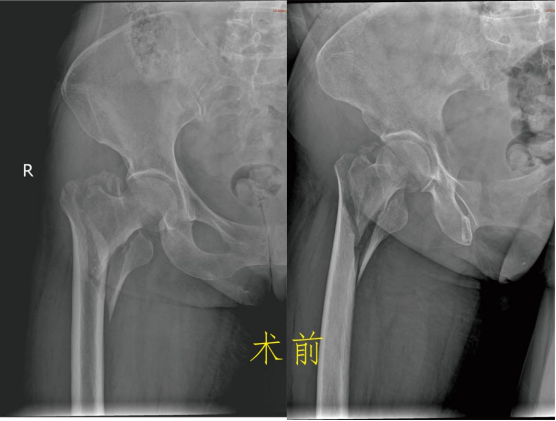

保守治疗 一般说的是卧床、牵引固定,等待骨折自己愈合。费用看似低廉,不用开刀出血,感觉上好像很安全,但老年人由于年纪大、体质差、新陈代谢水平低等原因,发生骨折后的愈合时间较长,所以保守治疗的缺点更多: 2.卧床时间长:髋部由于位置特殊,不像上肢骨折一样可以夹板石膏固定而不影响日常活动,一般髋部骨折通常要床边牵引制动2~3个月甚至更长,吃喝拉撒都在床上。看似很安稳,其实对于患者来说很痛苦。 3.并发症多:长期卧床容易产生褥疮;坠积性肺炎。泌尿系感染、深静脉血栓形成等,严重者危及生命。 4.治疗效果欠佳:单纯的牵引治疗很难保证复位质量。多数患者的骨折容易畸形愈合甚至不愈合,下肢短缩跛行,影响以后的生活质量。 5.加重骨质疏松:长期卧床、制动、骨量大量丢失,使原本的骨质疏松更加雪上加霜。 手术治疗 股骨颈骨折根据骨折移位情况,患者身体状况、年龄、预期寿命等因素,选择空心钉内固定术、人工半髋关节置换术或全髋关节置换术。股骨粗隆间骨折,一般采用闭合复位防旋髓内针内固定术或人工髋关节置换术。股骨粗隆下骨折主要是切开复位髓内针内固定术,很少使用钢板内固定术。 虽然老年髋部骨折术后死亡率高,国内外对其治疗方式争论不断,但研究表明。手术在降低死亡率、并发症发生率方面有明显优势。选择合适手术方式治疗老年髋部骨折可有效的降低死亡率、并发症发生率、改善患者生存质量。真正提高他们的生活质量。 更有多个研究发现,老年髋关节周围骨折的病人采取保守治疗之后的一年内死亡率接近50%!长期卧床引起的并发症,不管是褥疮、血栓、坠积性肺炎还是各种感染,都有可能会是致命的,这才是导致患者死亡的根本原因。 对此我们建议:在符合手术指征的前提下,老年髋部骨折应优选手术治疗。 九江市第一人民医院开发区分院/朱挺平